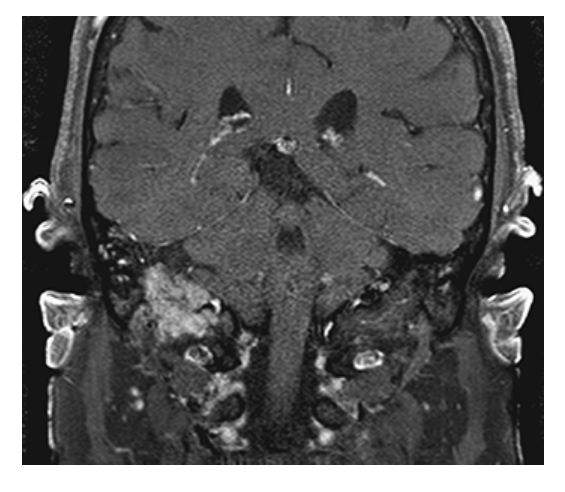

What does the figure show?

Glomus Tumor (Glomus Jugulotympanicum). Coronal FS T1W with gadolinium shows enhancing mass extending from right middle ear into jugular fossa representing a glomus jugulotympanicum tumor (paraganglioma).